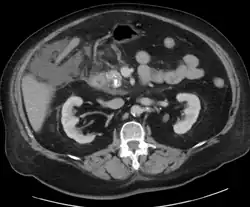

Calcified pancreatic duct stones with some free intra-abdominal fluid

A contrast-enhanced CT scan is usually performed more than 48 hours after the onset of pain to evaluate for pancreatic necrosis and extrapancreatic fluid as well as predict the severity of the disease. CT scanning earlier can be falsely reassuring.[34]